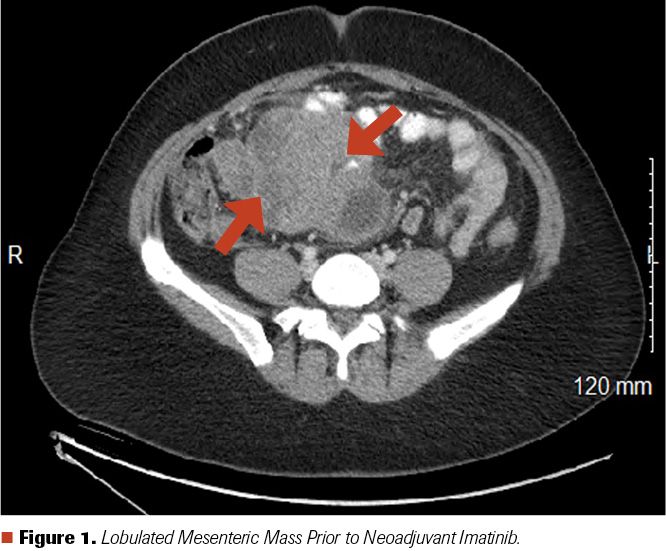

A 33-year-old White woman had been having some nonspecific intermittent abdominal pain for the past 2 years, which had been attributed to various different conditions including uterine fibroids, irritable bowel syndrome, fibromyalgia, and pelvic floor dysfunction. After visits to several different health care provider, a CT scan of the abdomen and pelvis eventually revealed a large lobulated mesenteric mass measuring 13.5 x 9.5 cm (Figure 1). A CT-guided biopsy of this mass revealed proliferation of epithelioid to spindled cells with moderate eosinophilic cytoplasm (Figures 2A and 2B). Immunohistochemical stains of the biopsy specimen were strongly positive for DOG1 (Figure 2C), CKIT, and CAM5.2; weakly positive for cytokeratin AE1/AE3; and negative for CK7, CK20, S100 protein, desmin, chromogranin, synaptophysin, CDX2, TTF1, PAX8, calretinin, and ER. WT1 was positive with cytoplasmic staining but negative with nuclear staining. The mitotic rate was estimated to be at least 2 per 50 high-power fields (HPF). No necrosis was identified.

Figure 1. Lobulated Mesenteric Mass Prior to Neoadjuvant Imatinib.